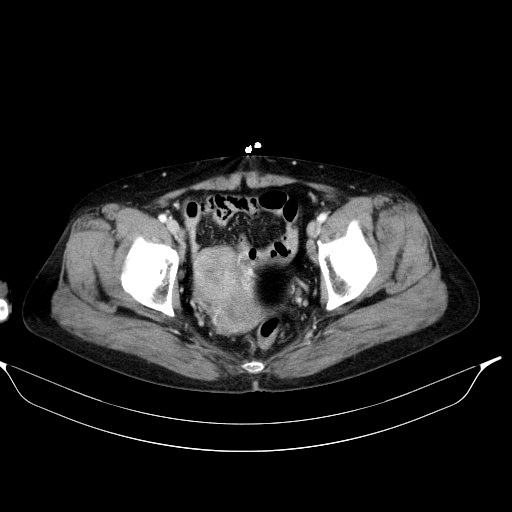

이쯤에서 이미 눈치채신 분들이 많겠지만, 앞서 CT 영상에서도 병변이 보이는데 그걸 놓치고 병변이 없다고 잘못 판단한 사례였습니다.

공기음영과 구분이 되지 않을 정도로 저음영을 보이는 fat-attenuated cyst가 자궁과 우측난소를 오른쪽으로 밀고 있었는데, 주변 장기들의 위치변화와 윤곽을 미처 확인하지 못하고 fat이 아닌 직장내 공기음영으로 잠시 착각했던 겁니다.

두번째 시행했던 초음파영상에서도 낭성병변이 여전히 확인되는 것을 보고, 제가 CT에서 뚜렷이 보였던 dermoid cyst가 있었다는 걸 뒤늦게 발견한 사례입니다. 지금 보면 정말 황당하고 썰렁한 실수였지만, 영상의 질이 제대로 확보된 질초음파영상에서 소변으로 가득찬 방광과 dermoid cyst는 쉽게 구별이 가능하다는 점을 생각하고 처음에 산부인과에서 촬영했던 질초음파영상을 좀 더 주의깊게 봤었다면 CT를 판독하면서 쓸데없는 수고와 위험을 초래하지 않았을 것입니다.